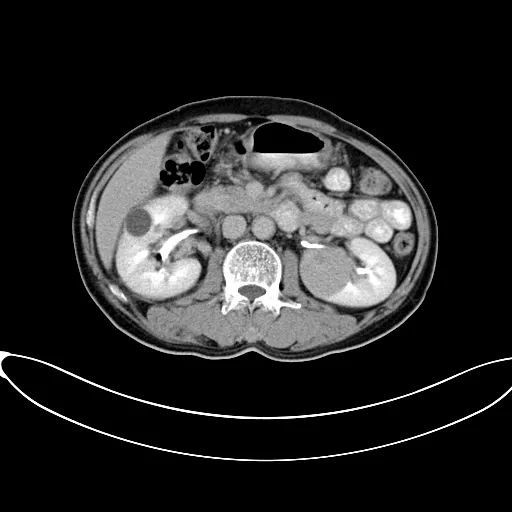

据安图叔叔的儿子回忆道,安图叔叔在体检前没有发现任何不适的症状,在体检后才知双肾占位,右肾下级占位 16.1*7.2cm,左肾下级肿瘤约3.7*4.3cm的情况。突如其来的病情让一家人陷入了恐慌,从未想过一个健康自律的人会突然间就被检出肾癌,还是双肾。安图叔叔的儿子激动地说道:“我当时一下子懵了,父亲之前表现那么健康,一查竟病得很重,为确诊我把父亲转接到新加坡就诊,那边的医生在看了我父亲的片子后都表示这是肿瘤,要做切除双肾然后再透析,对于我们来说,切肾这样的治疗方案对我们来说是无法接受的,父亲毕竟一把年纪,这样做法太伤他身体。”

2017年9月29日,从CT影像看到右肾情况更为严重。为减缓肿瘤增长的速度,专家进行商议后,最终决定由牛立志教授主刀为安图叔叔进行了右肾肿瘤冷冻消融术。手术开始后,牛立志教授在CT和超声引导下,同时使用两根冷冻针固定病灶,精准灭活肿瘤;术后很成功无不良反应。术后一周进行第二次双肾肿瘤冷冻消融术。安图叔叔儿子笑道:“当时真的很紧张,医生劝慰我无须担心,都交给他们,我们都很清楚知道父亲的病情,真的很感谢也很庆幸我父亲遇到复大的医护人员,免受开刀之痛。住院期间医护人员很尽心尽力的照顾父亲,手术的成功离不开他们的辛劳付出。”